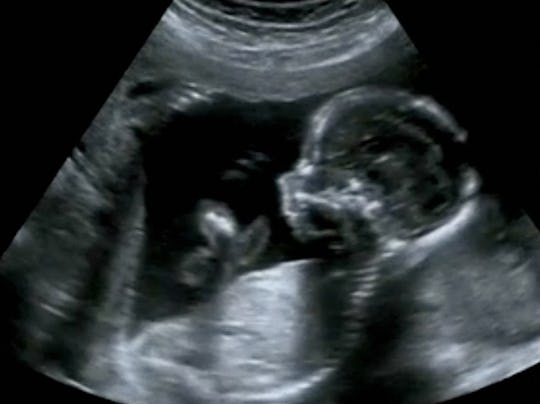

Mid shot of fetus worm dancing in womb. The babys movements also give the appearance that heshe is dancing. Incredible moment unborn baby disco-dances in its mothers womb during an ultrasound scan Amazing footage shows a baby seemingly boogying away.

Amazing Dancing Baby in the Womb. At another point the unborn baby waves hisher hand.

Tight shot of baby breakdancing within womb - Slow Motion.

Via Abel Mendiola Sotelo ViralHog. The baby is seen wriggling and waving its hands. He was well gone with old age and when he was administering the duties of a priest in the sanctum-sanctorum of the temple an Angel of the Lord appeared to him and said that his wife Elizabeth will bear a son who will redeem many from sin and baptize them with water. This amazing video shows tiny babies as young as 16 weeks dancing and singing as they hear music in the womb. The baby is enjoying the music and dancing inside. This is so amazing to watch. This womans womb got itself moving with the music.